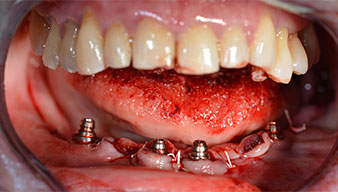

Para la planificación y la minimización del riesgo, se realizó una tomografía volumétrica tridimensional (TVD, Planmeca) que mostró que la calidad y la cantidad del tejido óseo era suficiente para la intervención quirúrgica y el tratamiento inmediato con el método Fast & Fixed. Siguiendo el protocolo de este método, se insertaron los implantes en la región de las piezas 35, 32, 42 y 45. Debido a la inclinación de hasta 45 grados de los implantes distales, el perfil de emergencia se desplazó hacia posterior y se generó un mayor polígono de soporte (fig. 3).

Tras la extracción de la dentición residual en el maxilar inferior, se realizó la incisión crestal en la región comprendida entre la pieza dental 37 y la 47.

A continuación, se identificó el agujero mentoniano (foramen mentale) como la estructura anatómica límite y se alisó el cortical de la cresta ósea con la pieza de mano recta y una fresa redonda grande (fig. 4).